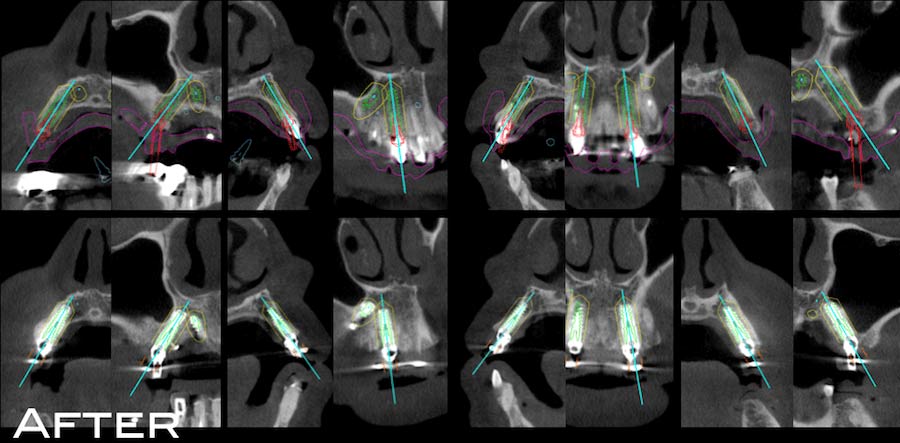

3Dシミュレーション

術前の3次元的なインプラント埋入計画と、術後のCT画像を比較すると、計画通りの位置にインプラントが埋入されている事が確認できる。この正確性はガイデッドサージェリーを行わなければ実現不能である。仮にインプラントの位置が0.5mmずれてしまうと、パーフェクトな審美性を獲得する事が出来ない。